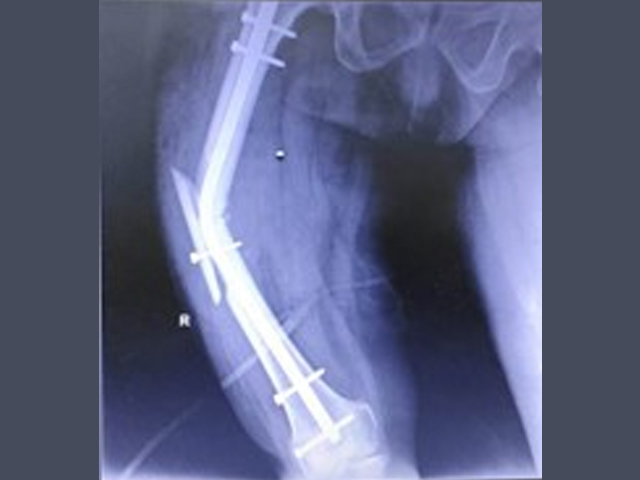

Trauma and Emergency Care:

The department operates a dedicated Level-I trauma center to manage accidents and emergencies. This facility provides prompt and effective treatment for patients with polytrauma, fractures, dislocations, and other musculoskeletal injuries. The trauma center is supported by an efficient Intensive Care Unit (ICU), anaesthetists, and Trauma Surgeons We also serve as a referral center for managing complications following trauma, such as infections, non-unions, and deformities.

Treatment of all routine, complex trauma and neglected trauma

✔  Corrective osteotomy in O.A knees and Limb lengthening